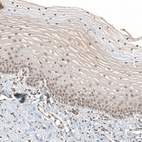

Immunohistochemical staining of human testis shows strong nuclear positivity in cells in seminiferous ducts.